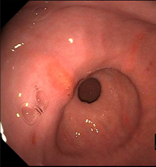

Glandular ulcers in a horse